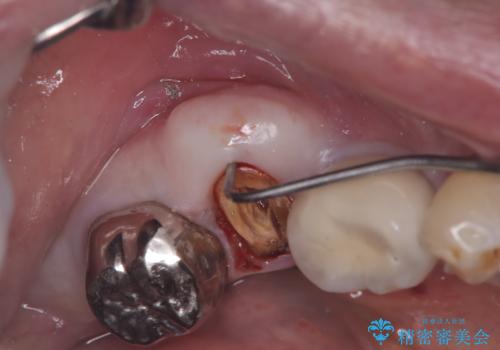

- 「歯を咬むと痛い」を主訴に来院された患者様です。 CTを撮ると歯根が縦に真っ二つに割れている状態で、歯周ポケットも10㎜を超える状態でした。

歯の保存は困難と診断しインプラントで治療を行いました。1Dayインプラントの適応だったので、抜歯した当日にインプラントを埋入しました。